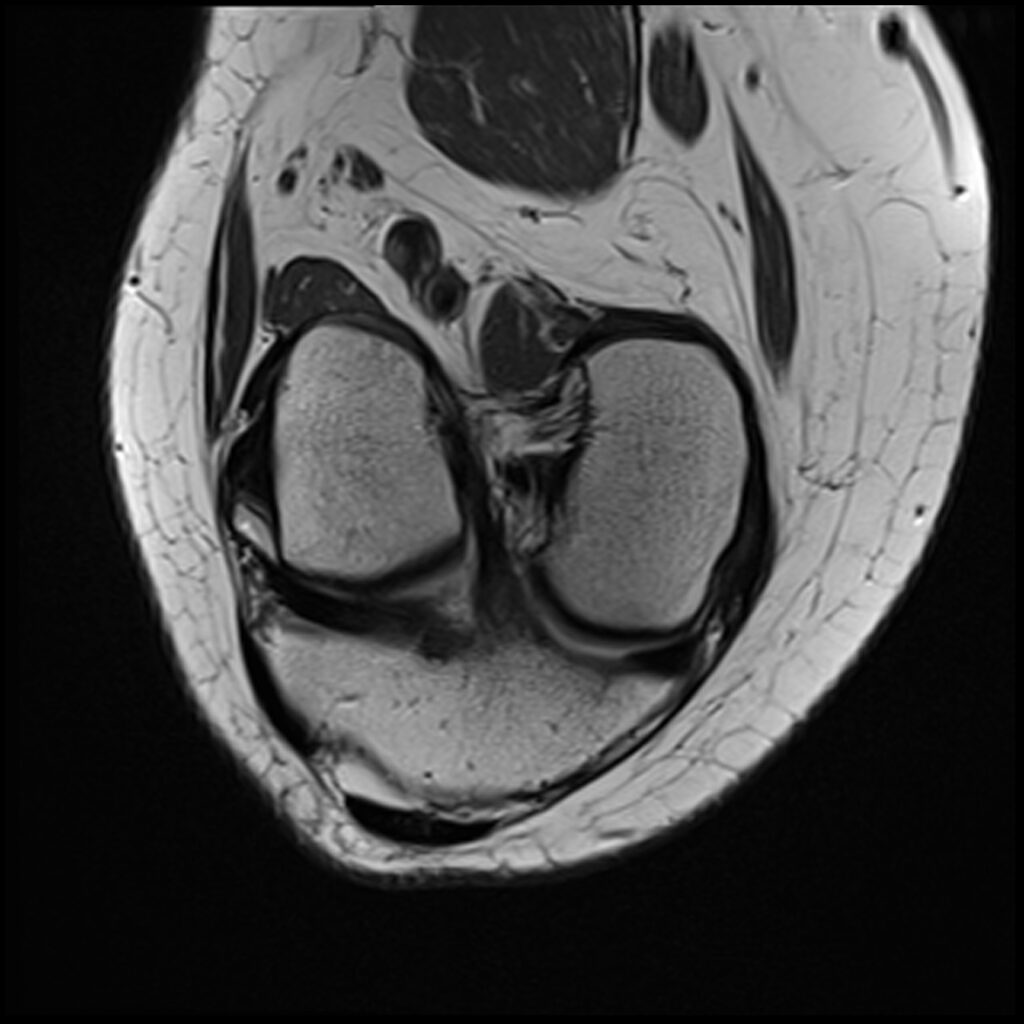

Patient C, age 44, was jumping on a trampoline when her foot got caught during rebound landing and forced the knee to extend and twist, tearing her ACL and medial meniscus and causing a Segond’s fracture, a posterolateral compression injury seen on the T2 sagittal MR images. Immediately upon becoming aware of her ACL injury, she asked my staff if she could put her “before & after” MR scans on my practice’s website after it healed. The initial treatment and aftercare were the same as patient D, aspirating any effusion and treating the posterolateral origin of the ACL. At 8-week follow-up, her knee was treated with hypertonic dextrose, with the collateral ligaments being treated with DGP. She was treated again at 16 weeks with another autologous PRP treatment of the knee joint, ligaments, and tendons. She was released to full sports and activities at 18 weeks post-injury. Subsequent MR scan revealed complete recovery of her ACL. Low grey signal replaced the original high signal intensity tear in the meniscus, appearing healed. Her knee was reported to be symptom-free at 5-year follow-up.

Patient C Before

Patient C After